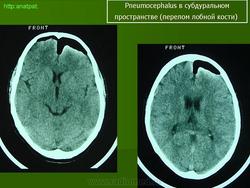

КТ-симптом горы Фудзи (Фудзиямы) помогает отличить напряженную пневмоцефалию от ненапряженной. Действительно, характерное разделение лобных долей не обнаруживается у пациентов с ненапряженной пневмоцефалией.

Напряженная пневмоцефалия характеризуется повышенным давлением воздуха в субдуральном пространсте. Повышенное давление воздуха является следствием клапана механизма, при котором воздух входит в субдуральное пространство через дефект в кости черепа, но выход воздуха заблокирован. Напряженная пневмоцефалия приводит к масс-эффекту и сдавлению лобных долей. Присутствие воздуха между лобными долями означает, что давление субдурального воздуха превышало поверхностное натяжение спинномозговой жидкости между лобными долями (Michel S.J.: Симптом горы Фудзи. Радиология, 2004, 232: 449-450).